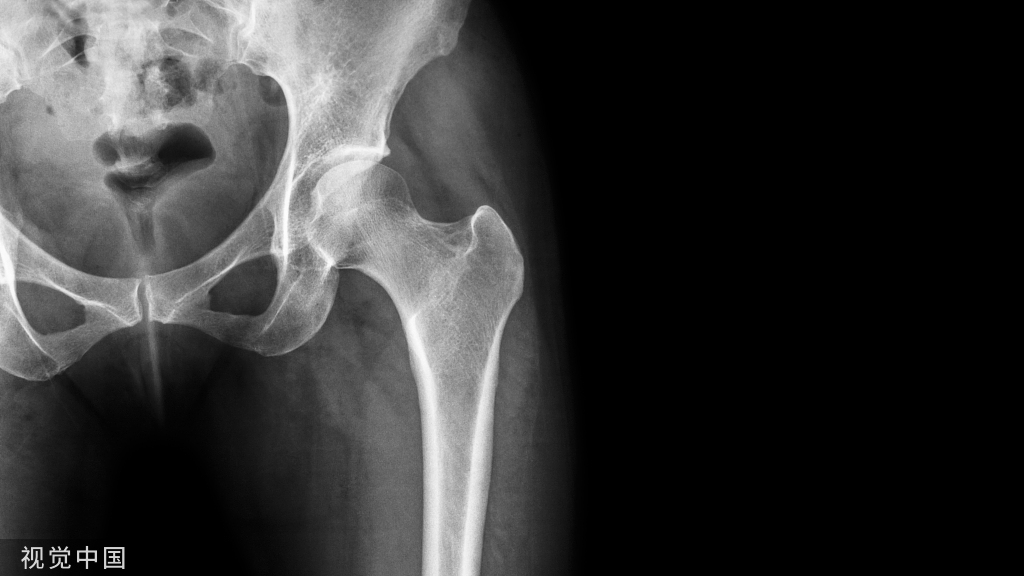

在老年人所有骨折中,髋部骨折是最严重的类型。髋部骨折因其预后差、并发症多、死亡率高的特点,在老年人中被认为是“生命中的最后一次骨折”。随着年龄的增长,老年人身体机能、协调性、反应能力下降,髋关节周围肌肉力量下降,同时体内钙流失严重,骨密度下降。当髋关节受到外力轻微撞击时,就会发生骨折。

近年来,随着人口老龄化的加速,老年人口的增加也相应导致髋部骨折的人数逐年增加。据统计,到2050年,全球髋部骨折病例预计将达到450万例(1990年为126万例),其中约一半发生在亚洲,尤其是中国。髋部骨折仅占所有骨质疏松性骨折的14%,但需要72%的总费用,预计到2025年,美国髋部骨折的费用将超过182亿美元。髋部骨折患者往往需要较长的恢复和康复时间,住院时间(LOS)的延长可能会增加长期卧床并发症的发生率,这直接导致较高的医疗成本,包括个人和社会医疗成本。在医疗资源有限和老年人口不断增长的情况下,髋部骨折患者的早期出院尤为重要。